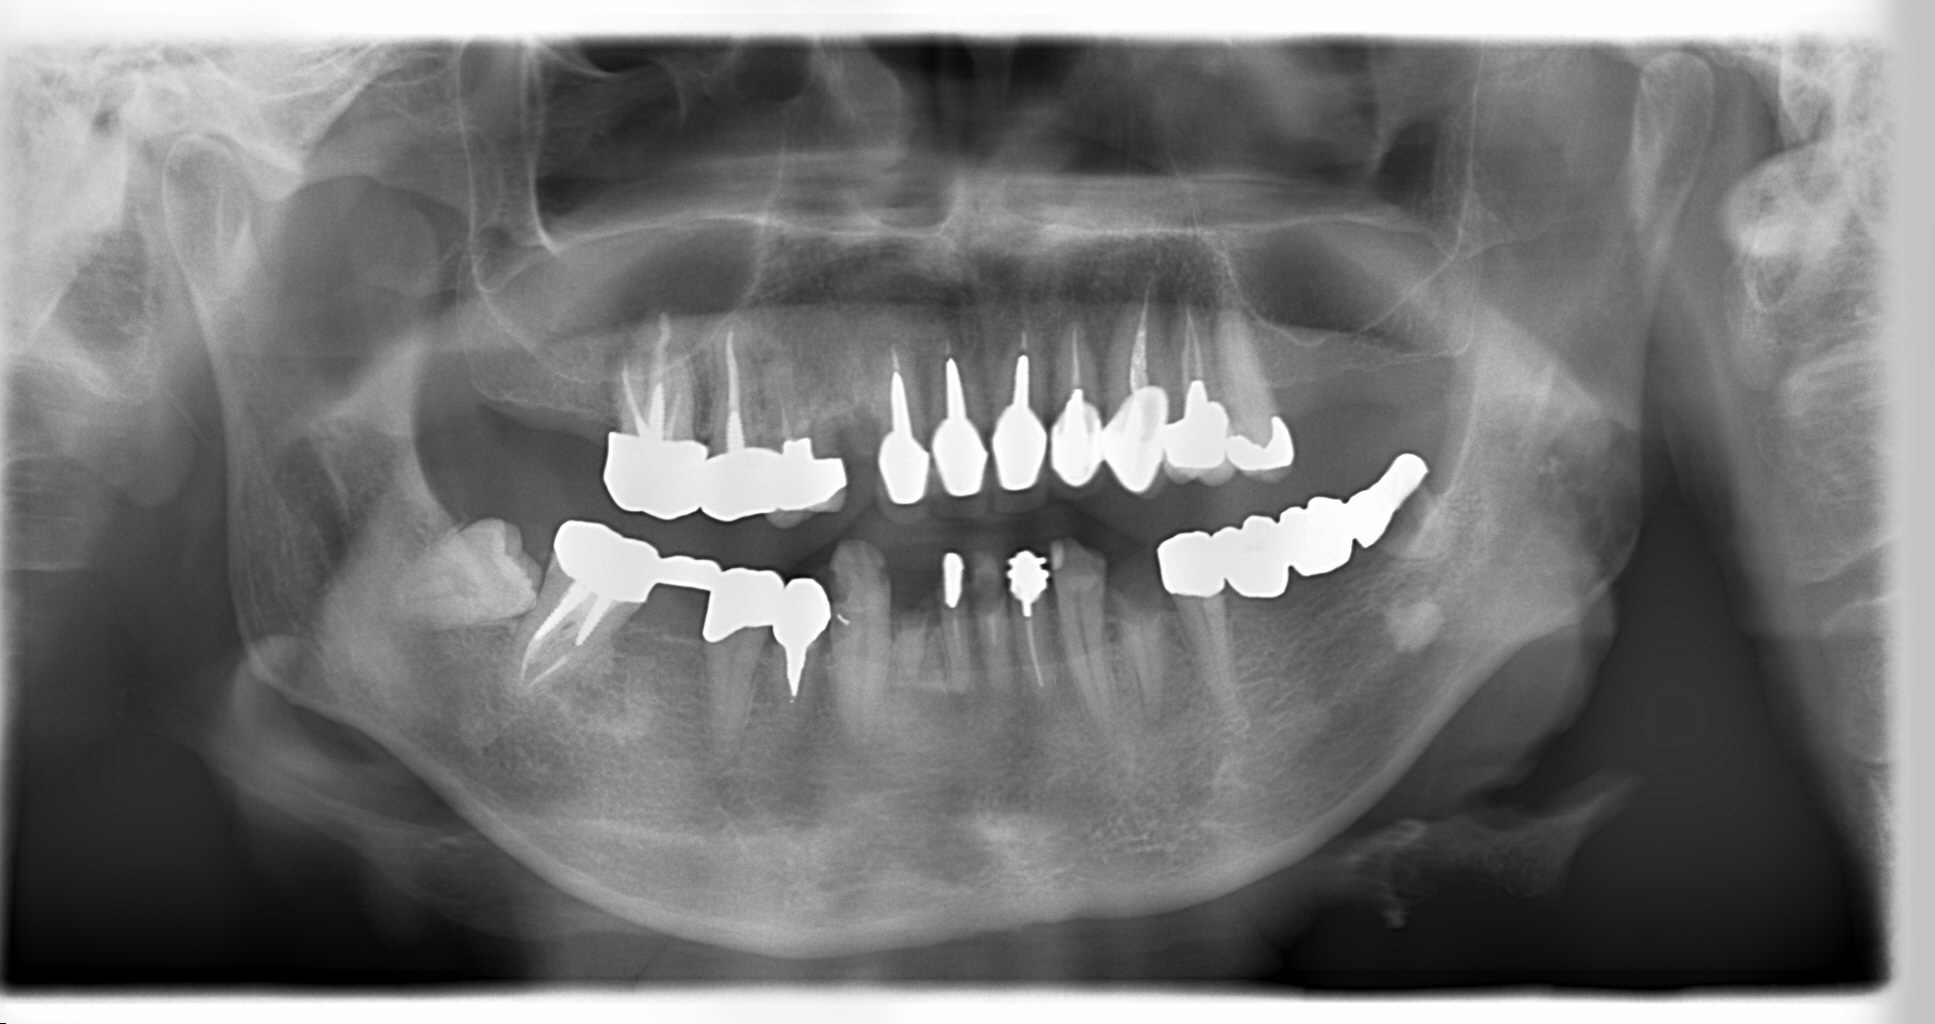

むし歯が大分進行して歯冠が無くなり、歯根だけになっている歯も多数認められます。

治療が困難である予後不良歯は抜歯し、保存可能な歯に対して、むし歯の治療、根管治療、仮歯の装着、クリーニング等を行っていきました。

辺縁骨より下方にむし歯が進行しており、抜歯と判断されるかもしれない歯に対しては、矯正を行うことで歯を挺出(歯を引き出す)し、クラウンを装着できるようにしました。

また、左下奥歯の欠損に対してはインプラントを埋入することで入れ歯を回避。